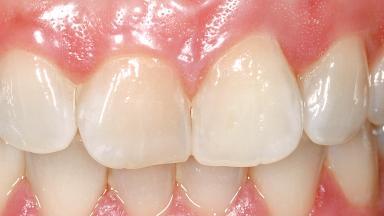

A 29-year-old female patient presented for treatment to replace the upper left central incisor tooth with an implant- supported restoration. The tooth had been intermittently symptomatic for the previous 12 months. The tooth had originally suffered trauma about 15 years previously. Several endodontic treatments had been performed, including an apicectomy procedure to retain the tooth. The patient was healthy and a non-smoker. She had reasonable expectations in regard to esthetic outcomes and the risk of marginal tissue recession following treatment. At medium smile, the gingival margins of the upper teeth were visible, with a display of 3 to 4 mm of the gingival margins. Gingival recession of tooth 21 and a discrepancy in the gingival levels between teeth 11 and 21 was observable during normal speech and smile.

Soft Tissue Anatomy Intact Defective

Soft Tissue Contour and Volume Slightly compromised